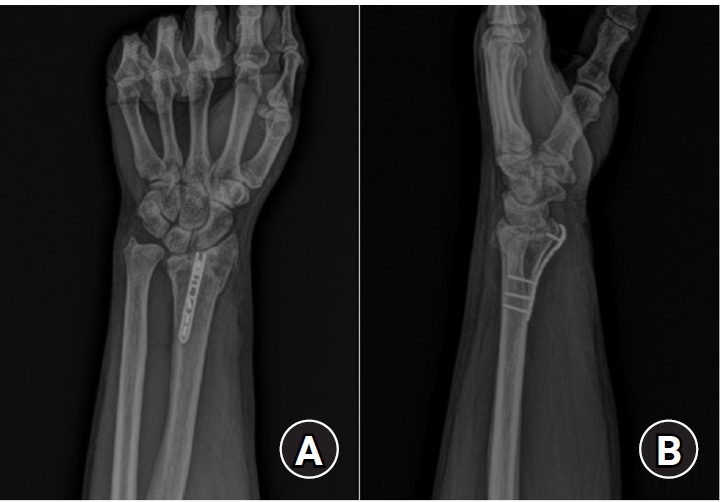

Fig. 2.

Postoperative radiographs (A) anteroposterior and (B) lateral: a 2.0 mm locking compression plate distal ulnar hook plate (Synthes) used for fixation in a distal radius fracture with a volar lunate facet fragment.

Fig. 2. Postoperative radiographs (A) anteroposterior and (B) lateral: a 2.0 mm locking compression plate distal ulnar hook plate (Synthes) used for fixation in a distal radius fracture with a volar lunate facet fragment.